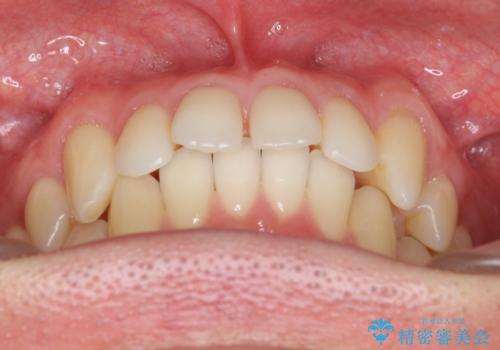

前歯のすき間 セラミックで綺麗に 最短で治療

長年コンプレックスだったすき間が閉じたとのことで、喜んでいただきました。

ただし、セラミックは欠ける特性があるため、夜はナイトガードを使用していただくことにしました。

- 51.7万円 (ジルコニアクラウン スタンダード11万円x4本、仮歯1.1万円x4本、ナイトガード 3.3万円)税込費用は治療当時の料金となります